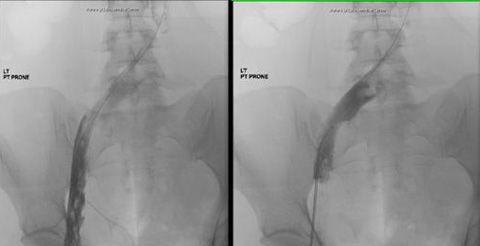

Residual thrombus (Figure 1) was noted in the origin of the left common iliac vein shortly after the procedure and required extensive catheter-directed infusion of tissue plasminogen activator. The following day additional mechanical thrombolysis was performed and the patient underwent post-procedure evaluation with intravascular ultrasound. A persistent round filling defect was noted at the inferior vena cava bifurcation with near complete occlusion of the right common iliac vein. There was progressive recurrence of thrombus in the left iliac venous system (Figure 2) and involvement of the right lower extremity, where a new clot was noted.

Figure 2